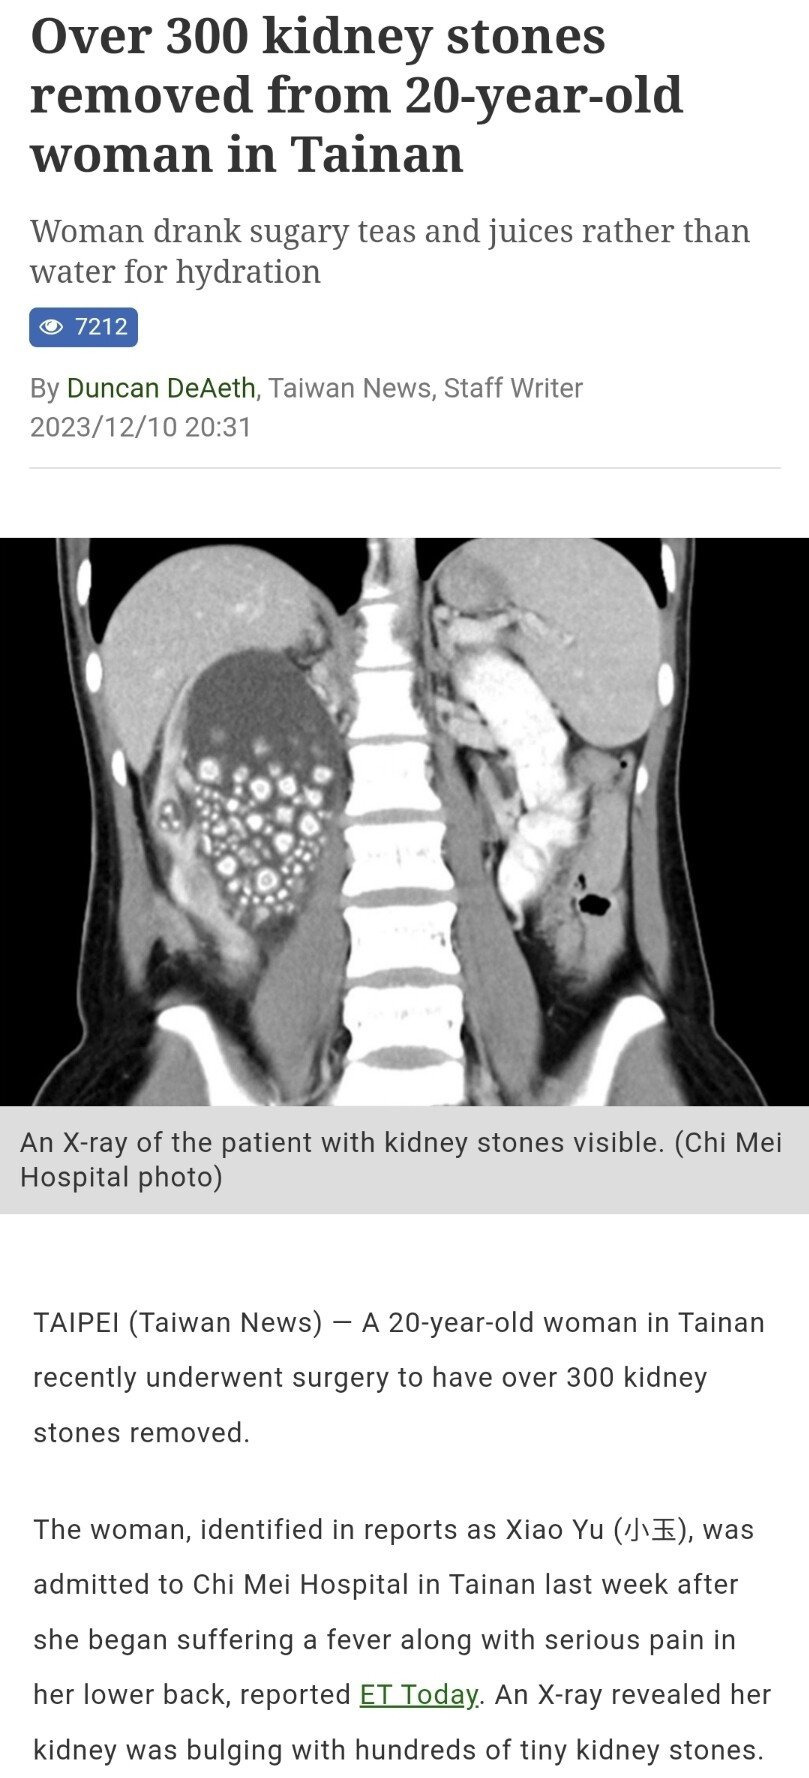

대만 타이난에 거주 중인 20살 여성

물 마시기 싫어서 버블티나 주스를 수년간 물 대신 마셨다가

갑자기 등쪽에서 극심한 통증이 느껴져 병원갔다가

신장결석 제거 수술했다고함